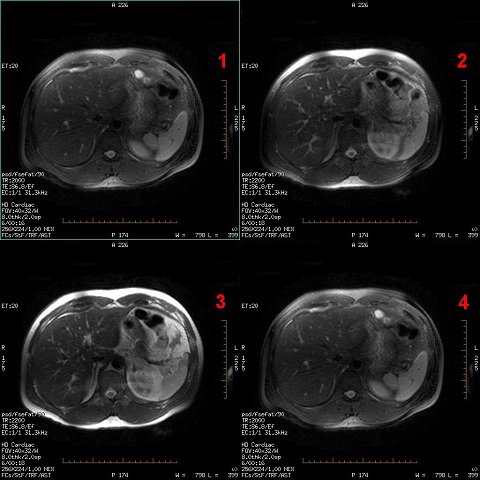

Fat Saturation Efficiency

Use Fat Saturation Efficiency to control the amount of fat that is saturated when either Fat SAT or Classic Fat SAT are selected from the Scan Parameters area. For more information, see Prescribe a chemical SAT pulse.

- The default setting is 0.65 and the range is from 0.5 to 1.0.

- Adjust the Fat Saturation value based on the amount of saturation desired from the fat signal. As the fat saturation value increases, more fat is suppressed:

- Set the value to 0.5 to make fat the brightest possible intensity.

- Set the value to 1.0 to make fat the darkest intensity.